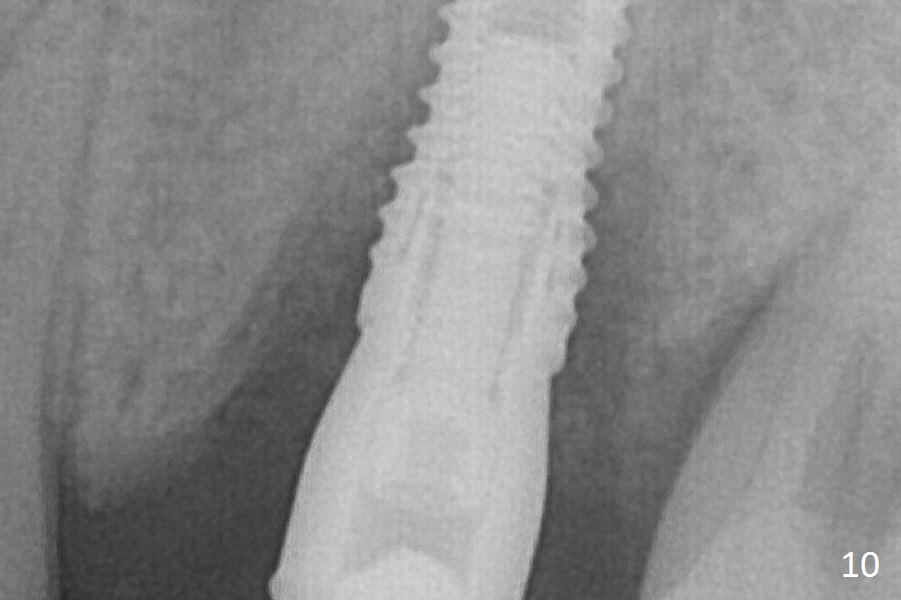

Bone density between #13 and 14 appears to increase 3 months postop (Fig.10). There seems to be more bone growth (i.e., decreasing gap) 6 months postop (Fig.12).